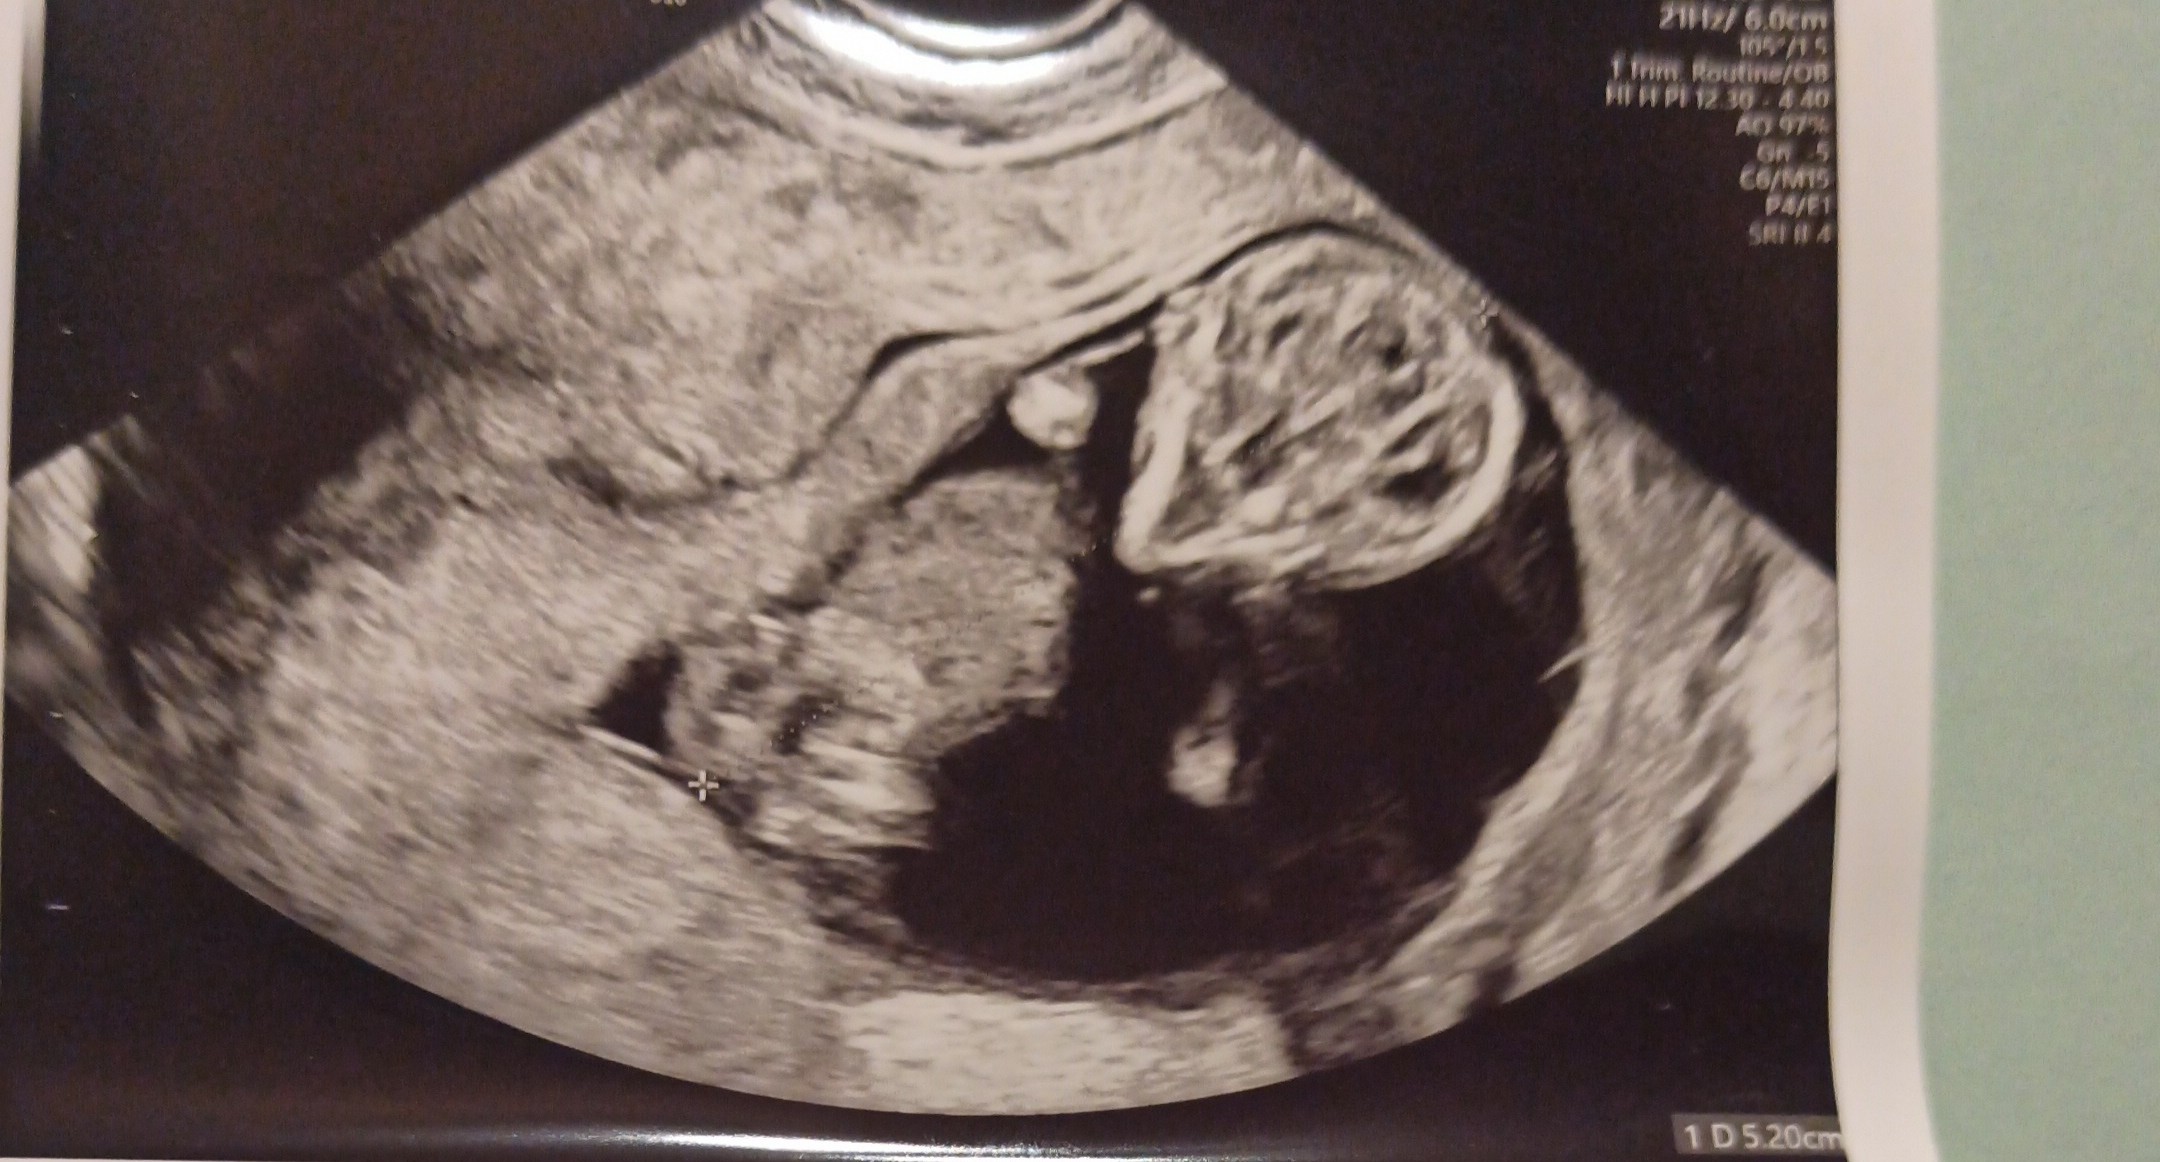

Hej dziewczyny, dodaje aktualizacje naszej sytuacji. 14.12 miałam wizytę u mojej gin. Objawy ciążowe się uspokoiły, teraz mam tylko wahania nastroju, ostatnie USG wskazywało, że zarodek ma 1,23cm i był to 7t3d, teraz powinnam być w 11t3d, ale wg USG wyszedł nam po pomiarach głowy i brzucha 12t5d czyli ciąża tydzień starsza. We wtorek mam badania prenatalne, bo to w sumie ostatni gwizdek. Trochę się uspokoiłam i nabieram nadziei, że będzie dobrze, w sumie wkraczam w 2 trymestr. Zobaczymy co wyjdzie 21.12, bo już chciałabym powiedzieć rodzinie. Według mojej doktor być może spodziewamy się drugiej córki, ale ze znakiem zapytania, bo między nogami nic nie widziała dlatego może być babeczka. Na badaniu dzidziuś spał i gin nie budziła maleństwa, pierwszy raz słyszałam bicie serca a moje waliło jak oszalałe, bo tak się bałam, że już go nie usłyszę. Ogólnie, rączki i nóżki są na swoim miejscu, stópki są, ilość wód prawidłowa, a dzidzia ma 5,2cm. Z przęjęcia zapomniałam zapytać o tą torbiel na jajniku czy się nie powiększa, ale zapytam na genetycznym. Wrzucę Wam zdjęcie z usg z prośbą o trzymanie kciuków na tą żabkę. Ja trzymam za Was wszystkie, żeby końcówka tego i przyszły rok był dla każdej w końcu tym szczęśliwym.

Załączniki

• IMG_20211217_132810.jpg

IMG_20211217_132810.jpg

395,2 KB · Wyświetleń: 64